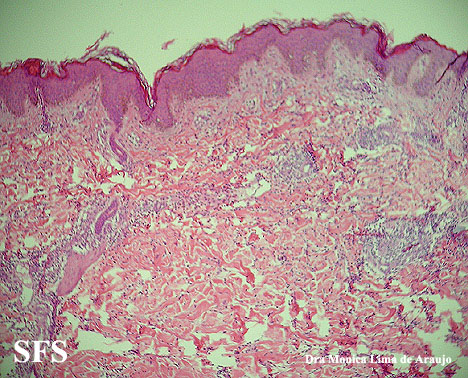

eosinophilic annular erythema